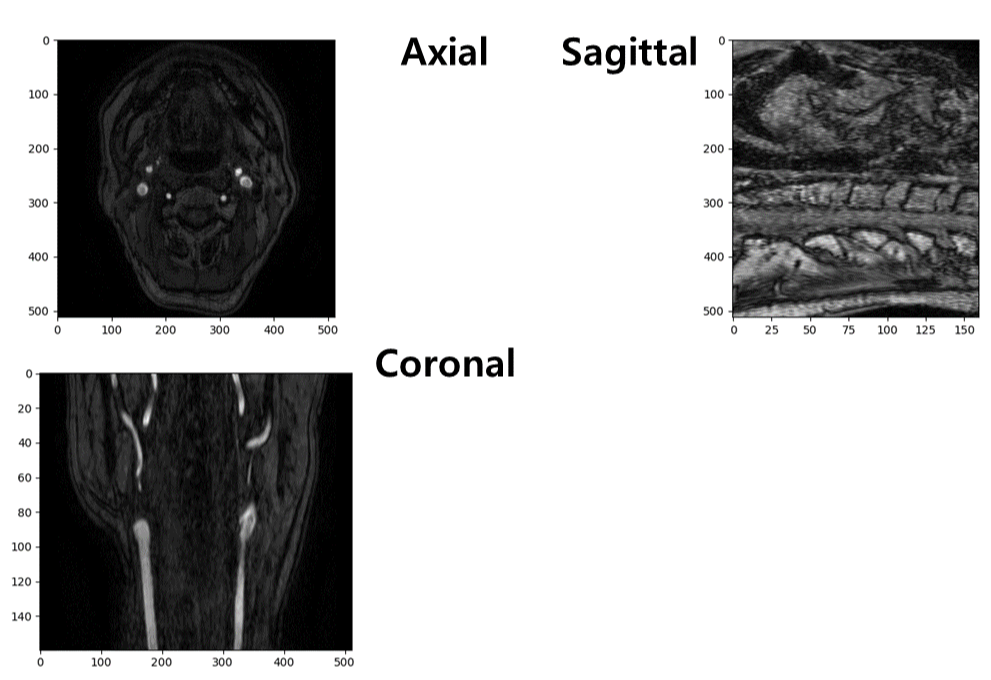

Multi Planar Reconstruction(MPR)

해부학적 평면을 기반으로 하여 MR, CT 등의 시퀀스 이미지를 시각화하는 방법인 Multi Planar Reconstruction을 통해 시각화를 진행해 보겠습니다.

위와 같이 Python에서 MPR 기반 시각화를 진행해 보겠습니다.

마지막은 3차원으로 구성한 데이터를 시각화하는 부분입니다. Subplot를 통해 하나의 창에 다수의 이미지를 시각화할 수 있게 하였고 Img_shape [0], Img_shape [1], Img_shape [2]를 통해 각각의 해부학적 평면의 중간에 위치한 이미지를 시각화할 수 있도록 하였습니다.

다음은 전체 코드의 결과 그림을 나타냅니다.

결과물을 자세히 보면 Radiant보다 늘어나 있거나 회전되어 있는 모습을 볼 수 있습니다. 해당 문제는 다음 글에서 다루어 보겠습니다.